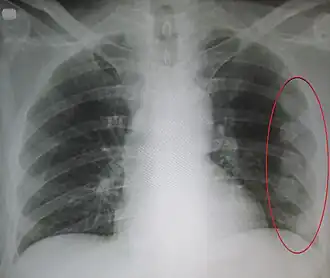

![]() Рентгенограмма грудной клетки. Обозначена область множественных старых переломов рёбер. | |

Проводят рентгенографию грудной клетки. Однако при данном методе не всегда удаётся выявить перелом. Поэтому диагноз перелома рёбер обычно устанавливают на основании клинических данных (анамнез, жалобы, объективные данные). Для исключения осложнений проводят клинический анализ крови и мочи.